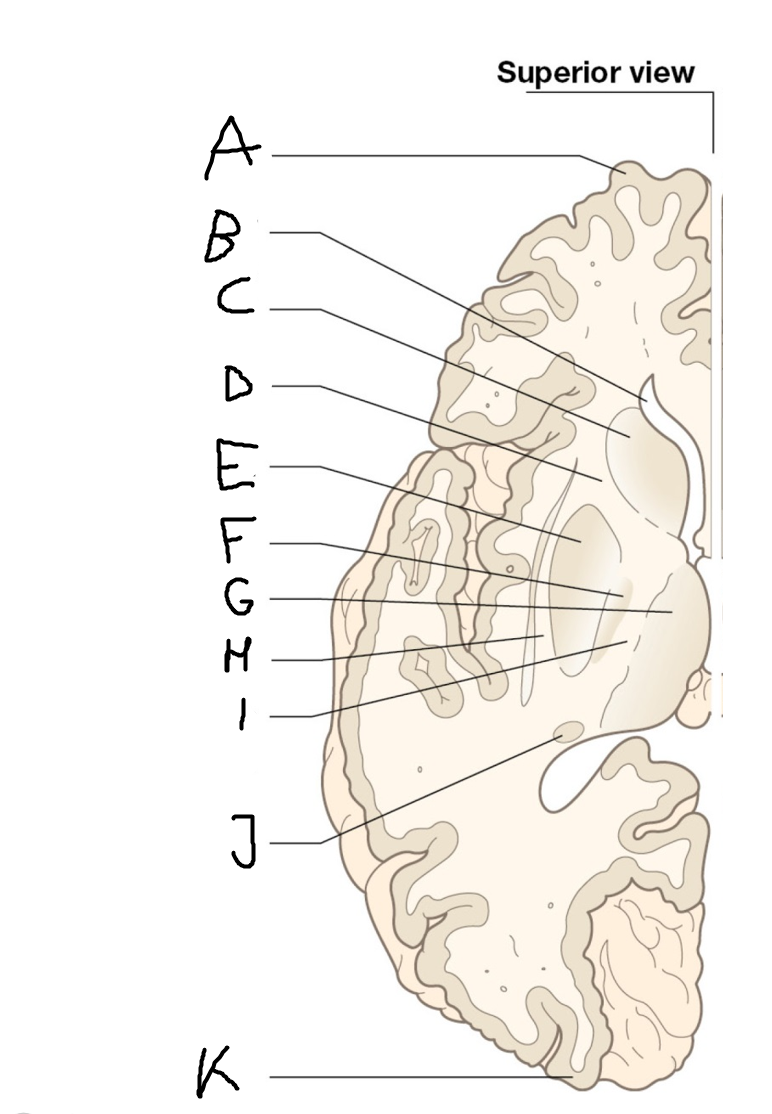

A

internal capsule (anterior limb)

B

caudate nucleus body

C

caudate nucleus head

D

putamen

E

caudate nucleus tail

F

thalamus

G

internal capsule (posterior limb)

B

anterior horn of lateral ventricle

C

head of caudate nucleus

D

internal capsule (anterior limb)

E

putamen

F

globus pallidus

G

Thalamus

H

External capsule

I

internal capsule (posterior limb)

J